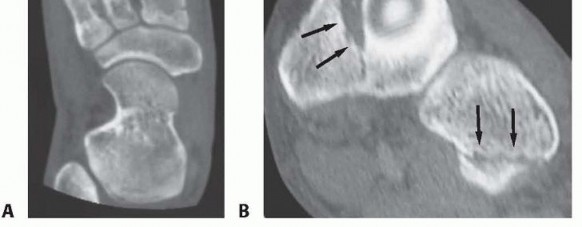

The bony elements of the medial three tarsometatarsal joints (medial, middle, and lateral cuneiforms and first, second, and third metatarsal bases) feature a unique trapezoidal shape in cross-section, creating a concave arrangement plantarly resembling a Roman arch (

FIG 1A

).

The second metatarsal is recessed between the medial and lateral cuneiforms in the axial plane and is positioned at the apex of the Roman arch in the coronal plane. It thus functions as the keystone of the entire midfoot complex (

FIG 1B

FIG 1

•

A.

Axial CT image depicting the Roman arch configuration of the tarsometatarsal joints.

B.

Anatomic specimen demonstrating the keystone of the Roman arch: The second metatarsal base is recessed between the medial and lateral cuneiforms (

black arrow